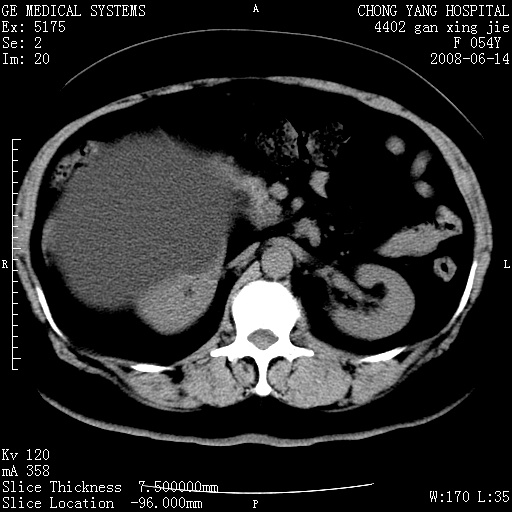

标题: CT14033:F54Y,来源哪? 外伤发现,自述既往无不适。 [打印本页]

标题: CT14033:F54Y,来源哪? 外伤发现,自述既往无不适。

1、脂肪肝。2、腹腔囊性占位,首考虑来源于右肾下极,其次考虑来源于肠系膜。

1、脂肪肝。2、腹腔囊性占位,首考虑肠源性囊肿或中肾管囊肿。

脂肪肝,巨大肾囊肿

1)脂肪肝。2)右肾下极巨大囊肿。

右中下腹部囊性肿块,与右肾下极关系密切,考虑右肾下极巨大外生性囊肿;脂肪肝。